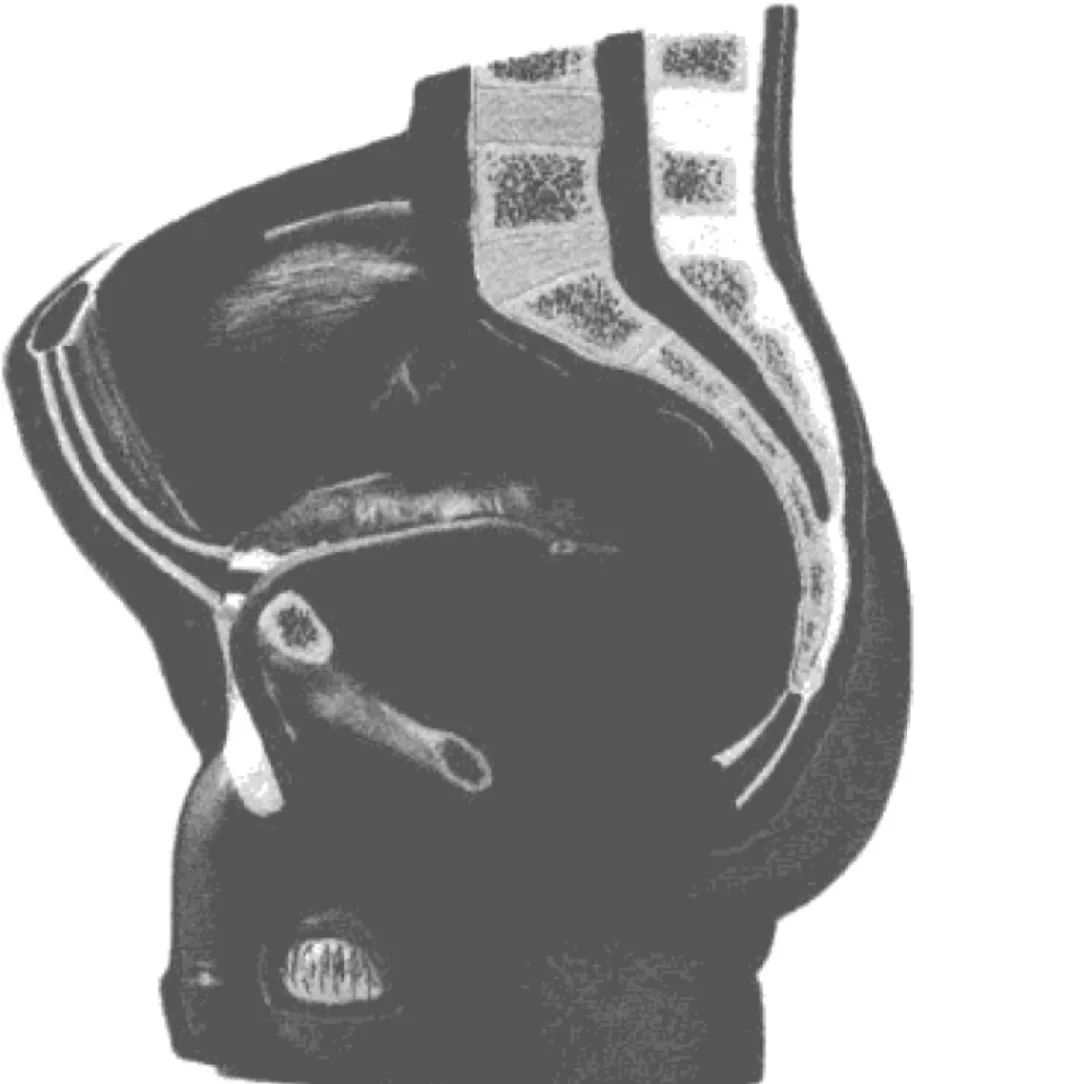

虽然说前列腺位于男性骨盆腔内,但它的位置在直肠前壁,距肛门约6~8厘米左右,所以用手指通过「菊花」就可以对前列腺进行触摸。医生可以通过这种方式判断前列腺是否有肿大或者外形上的变化。

图中金黄色的就是「栗子」一般的前列腺